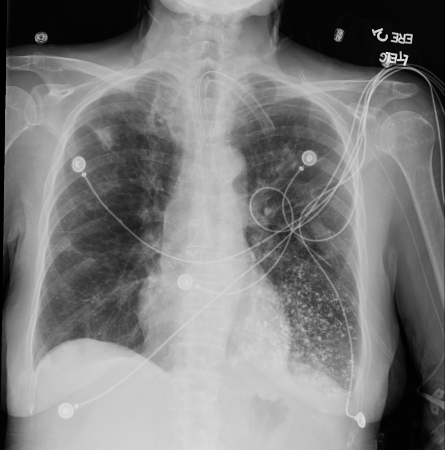

[Figure caption and citation for the preceding image starts]: Aspiración de bario. Se produjo una ingesta de bario en una mujer de 53 años. Las imágenes revelaron material hiperdenso centrado en la vía respiratoria en el lóbulo inferior izquierdo compatible con bronquiolitis por aspiración de bario. Se confirmó una fístula traqueoesofágicaDe la colección del Dr. Augustine Lee; utilizado con el permiso de la Fundación Mayo para la Educación e Investigación Médica, todos los derechos reservados [Citation ends].